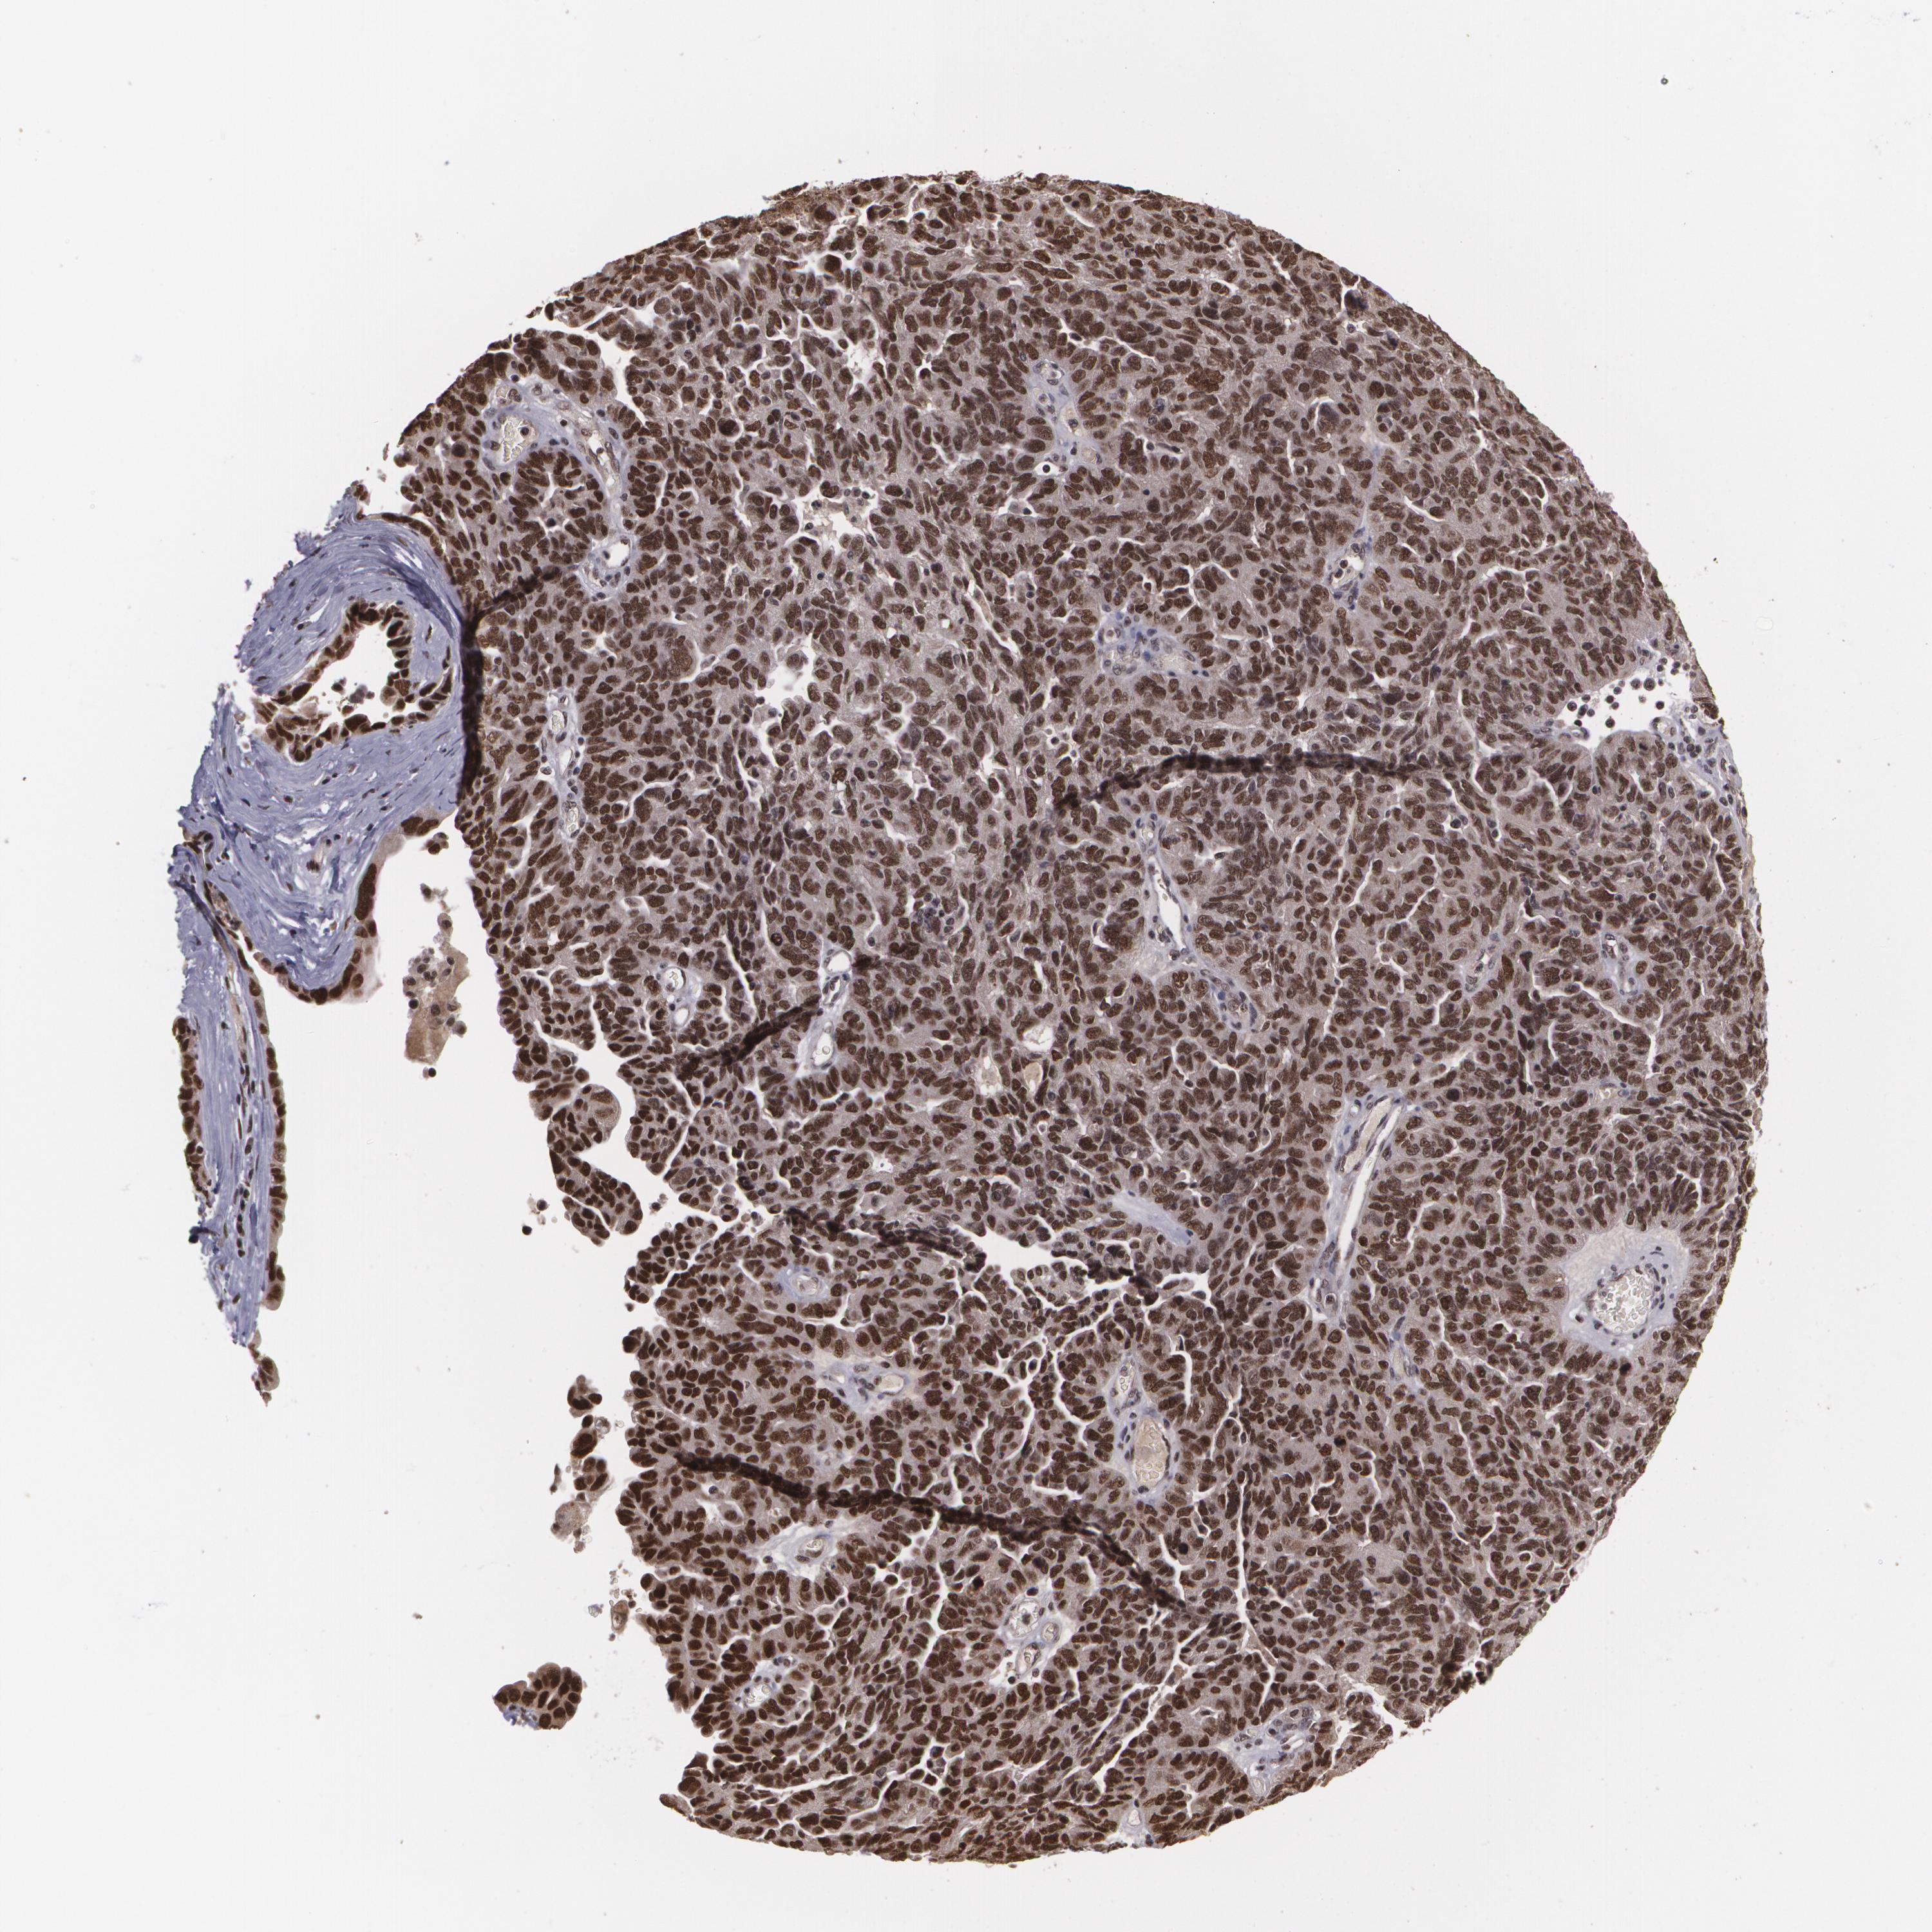

OVARIAN CANCER - Protein expressioni

A mouse-over function shows sample information and annotation data. Click on an image to view it in a full screen mode. Samples can be filtered based on level of antibody staining by selecting one or several of the following categories: high, medium, low and not detected. The assay and annotation is described here.

Note that samples used for immunohistochemistry by the Human Protein Atlas do not correspond to samples in the TCGA dataset.

Antibody stainingi

Antibody staining in the annotated cell types in the current human tissue is reported as not detected, low, medium, or high, based on conventional immunohistochemistry profiling in selected tissues. This score is based on the combination of the staining intensity and fraction of stained cells.

Each image is clickable and will lead to virtual microscopy that enables deeper exploration of all samples and also displays staining intensity scores, fraction scores and subcellular localization as well as patient and tissue information for each sample.

Antibody CAB002003

Staining

High

Medium

Low

Not detected

Intensity

Strong

Moderate

Weak

Negative

Quantity

>75%

75%-25%

<25%

None

Location

Nuclear

Cytoplasmic/membranous

Cytoplasmic/membranous,nuclear

Cystadenocarcinoma, mucinous, NOS

Carcinoma, endometroid

Cystadenocarcinoma, serous, NOS